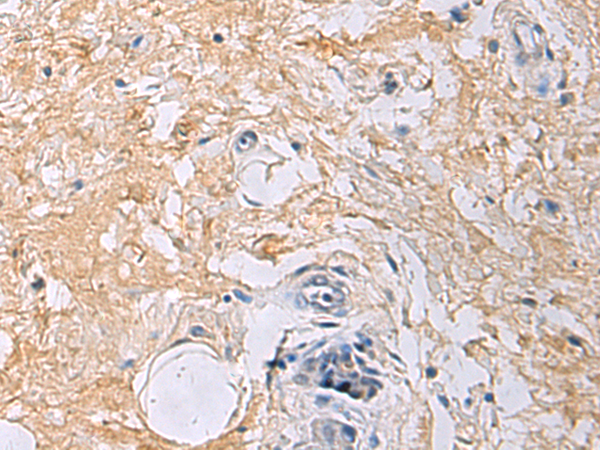

IHC positive control:

Human gastric cancer

IHC Recommend dilution:

50-100